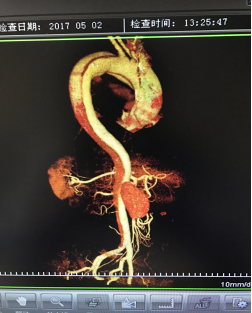

5月2號劉大伯照常早起干活,突然胸部劇烈疼痛,難以忍受,全身大汗,同時伴有右上肢發(fā)涼,他心想這次心絞痛比之前嚴重的多啊,趕緊叫上孩子到吉林國文醫(yī)院心血管內(nèi)科住院,患者長期高血壓病史,血壓一直控制不理想,大夫給他做了檢查,測左上肢血壓:82/45mmHg,右上肢血壓測不出,心率52次/分,右側(cè)肱動脈、尺動脈、橈動脈搏動消失,左側(cè)股動脈搏動較右側(cè)弱?!霸懔耍p側(cè)血壓差別這么大,是不是主動脈夾層了?”,接診大夫趕緊找來李主任,李主任反復(fù)詢問患者病情,表情突然凝重起來,患者胸痛這么明顯,血壓低的厲害,主動脈夾層的可能性很大。二話不說,李主任立即聯(lián)系影像科的醫(yī)生準備做主動脈CTA,移動患者做檢查的過程大夫們非常小心,嚴密監(jiān)測患者血壓變化情況。兩個小時后結(jié)果出來了,主動脈夾層從升主動脈一直撕裂到左側(cè)髂總動脈?。?!

從開始學醫(yī)到現(xiàn)在已經(jīng)快9年了,主動脈夾層患者也見過一些,但像劉大伯這種危險類型的還是第一次見到,心里真的為他捏把汗,撕裂的主動脈隨時都有可能破裂,生命隨時可能終止,要知道主動脈夾層的死亡率非常的高,約50%的患者發(fā)病后48小時死亡,約90%的患者發(fā)病1個月內(nèi)死亡。

李主任詳細的與劉大伯的女兒交代了病情,手術(shù)是挽救生命的唯一辦法,為了劉大伯的一線生機,我們積極聯(lián)系了我省權(quán)威的心血管外科,并做了詳細的匯報,兩家醫(yī)院對此非常重視,為劉大伯開通了綠色通道,安全的把他總到上級醫(yī)院,當天便給他進行血管置換及覆膜支架植術(shù)。他術(shù)后恢復(fù)的很好,后來劉大伯的女兒看望我們,感嘆道:沒想到國文醫(yī)院心內(nèi)科應(yīng)急能力這么高,在那么短的時間內(nèi)診斷明確,才給了我的老父親手術(shù)的機會。